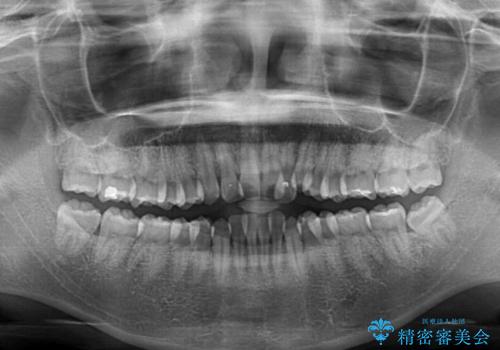

- 前歯のデコボコと口元の突出感を気にして来院された患者様です。

上下左右第一小臼歯4本を抜歯し、ワイヤー装置にて口元を引っ込めるよう矯正治療を行うこととしました。